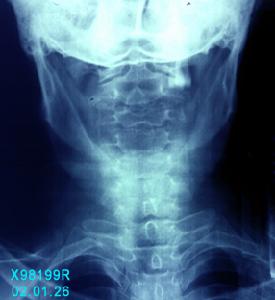

1.顱骨X線攝片能t解有無顱骨骨折,對判斷頭部著力部位、出血來源和血腫的位置、類型有幫助。